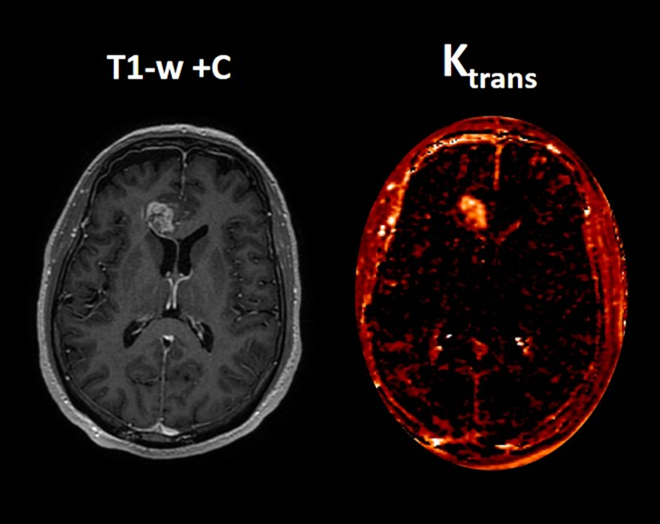

Beyond the Grayscale: How Quantitative MRI is Rewriting Neuroradiology

By Christos Tsiotsios, MSc. — Instructor & MRI Specialist Medical imaging is undergoing a major transformation. For decades, radiology has relied primarily on visual interpretation — radiologists ...